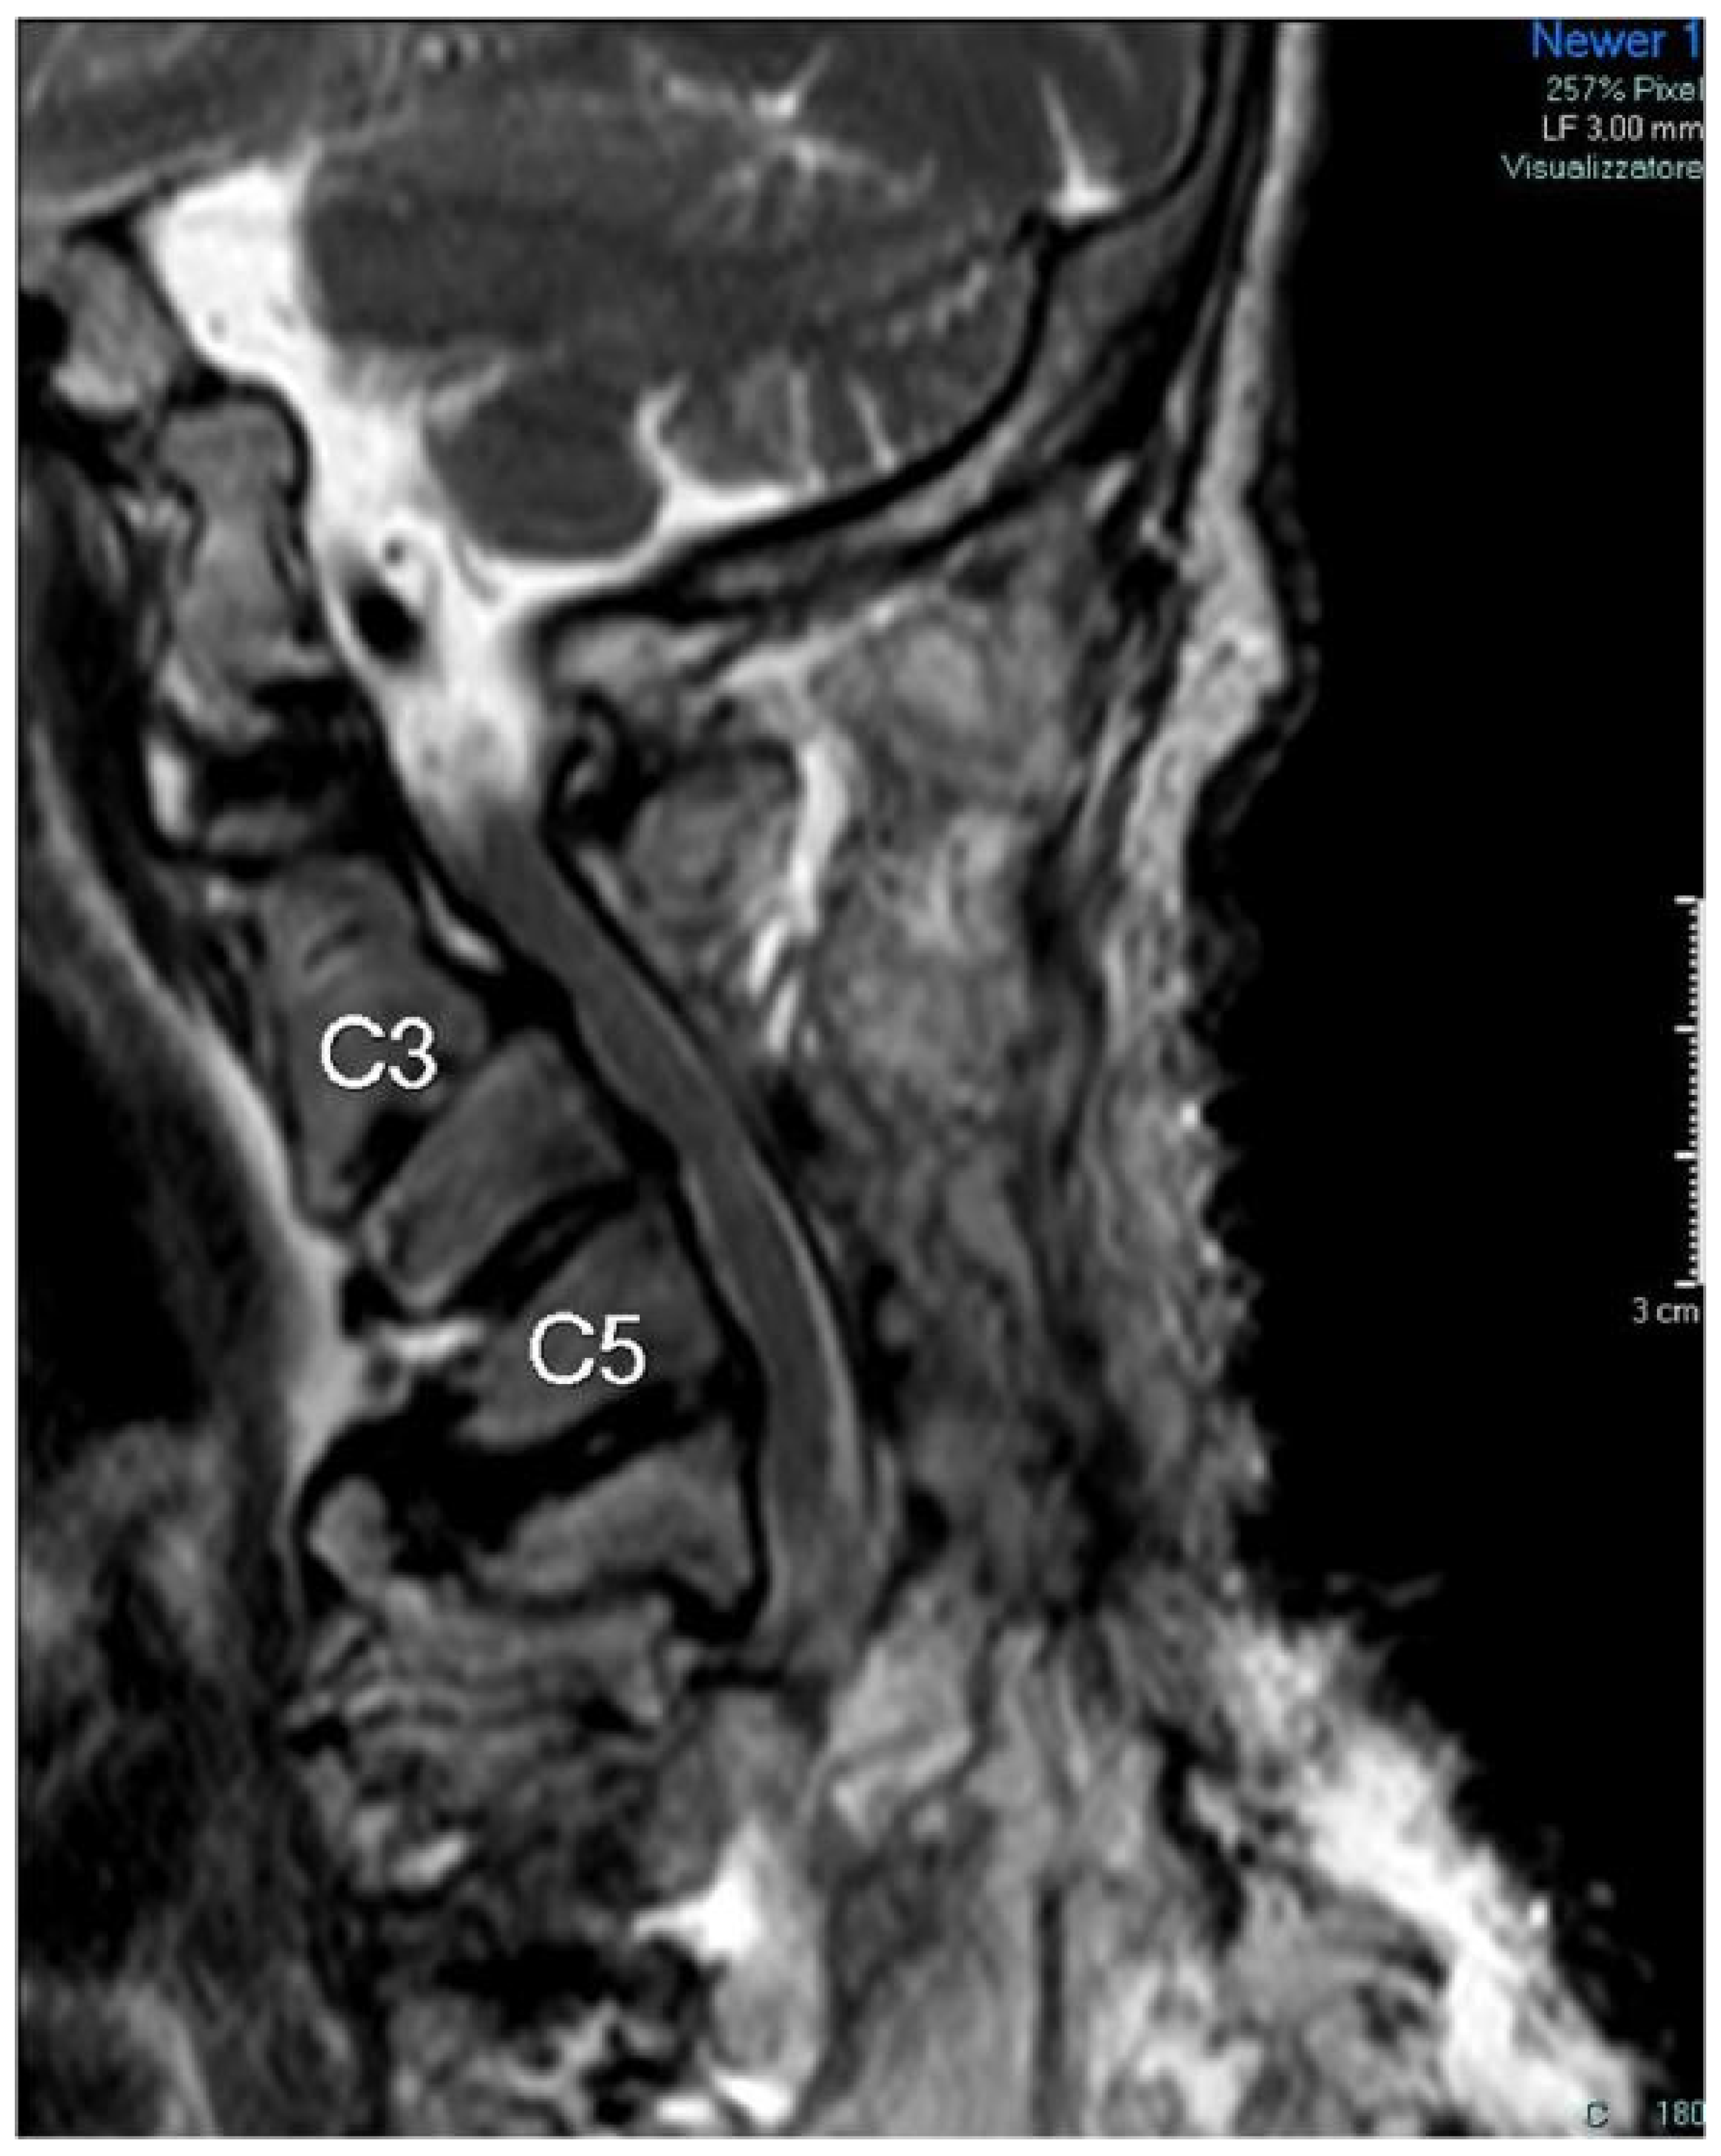

Figure 8.

MRI examination at 20 months after surgery. The third (C3) and fifth (C5) cervical vertebrae are indicated by labels.

Twenty months after surgery, the patient received clinical and radiological examinations. The MRI showed effective decompression of the spinal cord (Figure 8), and the patient could walk with one stick for about 50 m and reported a significant improvement in upper limb movements.